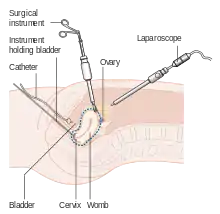

Surgery

The initial treatment for endometrial cancer is surgery; 90% of women with endometrial cancer are treated with some form of surgery.[23] Surgical treatment typically consists of hysterectomy including a bilateral salpingo-oophorectomy, which is the removal of the uterus, and both ovaries and Fallopian tubes. Lymphadenectomy, or removal of pelvic and para-aortic lymph nodes, is performed for tumors of histologic grade II or above.[16] Lymphadenectomy is routinely performed for all stages of endometrial cancer in the United States, but in the United Kingdom, the lymph nodes are typically only removed with disease of stage II or greater.[15] The topic of lymphadenectomy and what survival benefit it offers in stage I disease is still being debated.[22] In women with presumed stage I disease, a 2017 systematic review found no evidence that lymphadenectomy reduces the risk of death or relapse of cancer when compared with no lymphadenectomy.[65] Women who undergo lymphadenectomy are more likely to experience systemic morbidity related to surgery or lymphoedema/lymphocyst formation.[65] In stage III and IV cancers, cytoreductive surgery is the norm,[16] and a biopsy of the omentum may also be included.[66] In stage IV disease, where there are distant metastases, surgery can be used as part of palliative therapy.[22] Laparotomy, an open-abdomen procedure, is the traditional surgical procedure; however, in those with presumed early stage primary endometrial cancer, laparoscopy (keyhole surgery) is associated with reduced operative morbidity and similar overall and disease free survival.[66] Removal of the uterus via the abdomen is recommended over removal of the uterus via the vagina because it gives the opportunity to examine and obtain washings of the abdominal cavity to detect any further evidence of cancer. Staging of the cancer is done during the surgery.[67]

The few contraindications to surgery include inoperable tumor, massive obesity, a particularly high-risk operation, or a desire to preserve fertility.[67] These contraindications happen in about 5–10% of cases.[22] Women who wish to preserve their fertility and have low-grade stage I cancer can be treated with progestins, with or without concurrent tamoxifen therapy. This therapy can be continued until the cancer does not respond to treatment or until childbearing is done.[68] Uterine perforation may occur during a D&C or an endometrial biopsy.[69] Side effects of surgery to remove endometrial cancer can specifically include sexual dysfunction, temporary incontinence, and lymphedema, along with more common side effects of any surgery, including constipation.[9]